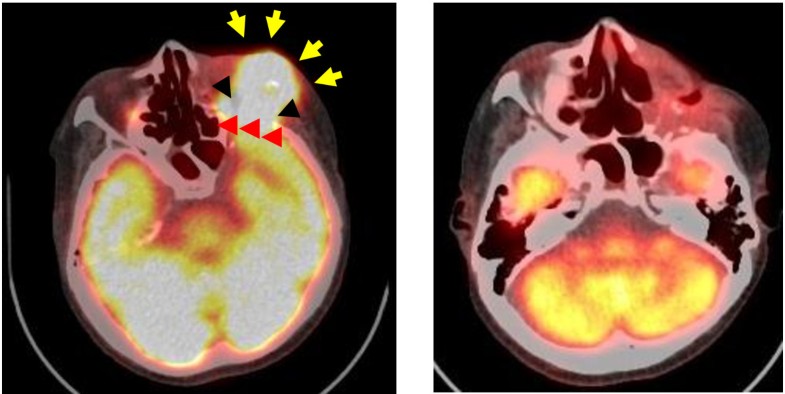

Figure 3

Contrast-enhanced T1-weighted MRI of representative glioblastoma patient and 18 F-labeled BPA-PET image after initial debulking surgery. The patients received 18 F-BPA-PET to assess the distribution of BPA and to estimate the boron concentration in tumors before BNCT without direct determination of boron concentration in the tumor. The lesion to normal brain (L/N) ratio of the enhanced tumor was 7.8 in this case. Note that even the periphery of the main mass, i.e., the infiltrative portion of the tumor, showed BPA uptake. The L/N ratio of BPA uptake can be estimated from this study and dose planning was done according to this L/N ratio, and if the L/N ratio was more than 2.5, then BNCT was initiated. 18 F-BPA-PET accurate BPA provided an accurate estimate of the accumulation and distribution of BPA as previously reported [64, 65].

Figure 4

18 FDG-PET study prior and 6 months after BNCT of a 56 year-old male patient with recurrent squamous cell carcinoma of the maxilla. A: FDG accumulated in the left orbital region (arrows) and frontal lobe of brain (arrow heads). B: No accumulation of FDG-PET was detected 6 months after BNCT and the patient was disease free for 61 months at the time of the original report. Photographs are from Applied Radiation and Isotopes, 67:S37-S42, 2009.